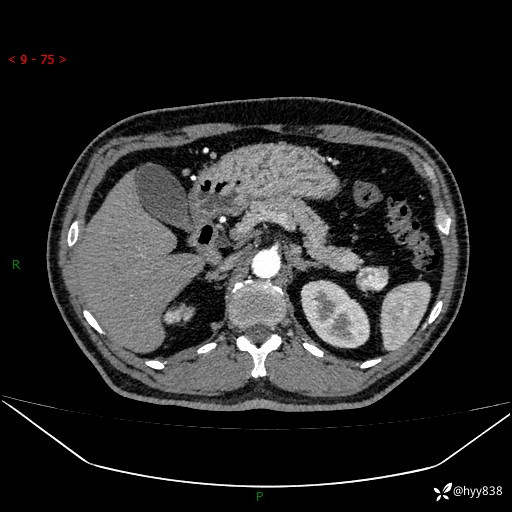

胰腺CT平扫